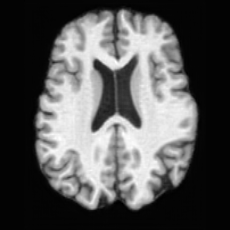

Figure 4: Qualitative results of USB on generation tasks. (a) unconditional generation, illustrating USB’s capability to generate lesion masks with diverse locations and complex shapes, together with their corresponding pathological brain images; (b) conditional generation, showing USB’s ability to generate unlimited pathological brain images conditioned on varying lesion masks.

Unconditional Generation. Fig. 4 (a) presents examples of paired lesion masks and brain images generated by USB. Notably, although the paired lesion-brain generation begins unconditionally from random noise, USB produces lesion masks exhibiting diverse locations, sizes, and shapes, while simultaneously generating anatomically coherent brain images with embedded pathological patterns that spatially correspond to the generated lesions within each pair.

In Tab. 1, we present the first quantitative benchmark evaluation of both generation tasks. For the unconditional generation task, we generated 256 paired lesion–brain samples for each lesion type (stroke and WMH). For the conditional generation task, we used masks from the ATLAS and ISLES test sets as stroke lesions, and masks from the ADNI test set as WMH lesions. Notably, for each lesion type, the unconditional generation achieved superior quantitative performance, highlighting that the paired diffusion mechanism effectively generates coherent lesion-brain pairs through joint modeling between USBbrain and USBlesion. Additional generation results are provided in Suppl. A.